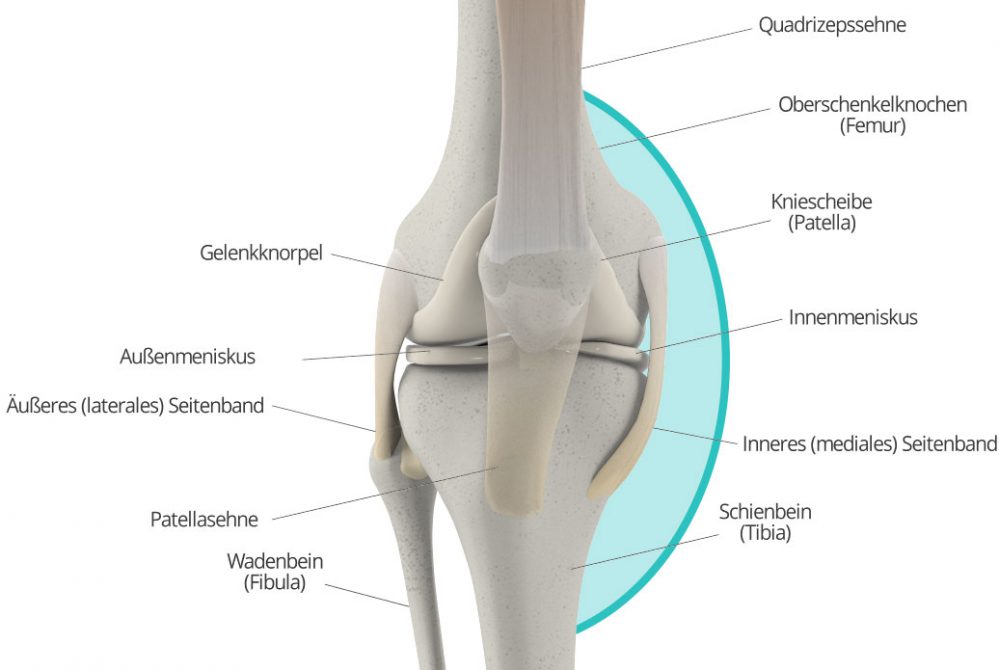

Aus dem Auftreten des Knieschmerzes an der Innenseite des Knies kann man noch keine eindeutige Diagnose ableiten: Zwar ist er oft ein Zeichen dafür, dass der Innenmeniskus geschädigt ist; doch auch andere Ursachen kommen infrage, beispielsweise eine Schleimbeutelentzündung, eine Sehnenreizung oder ein Sehnenschaden an der rückseitigen Oberschenkelmuskulatur (sog. Kniebeuger). Auch allgemeiner Gelenkverschleiß kann unter gewissen Umständen Schmerzen an der Knieinnenseite verursachen. Auch hier ist also eine genaue Untersuchung durch den Facharzt unabdinglich, um eine eindeutige Diagnose zu stellen.

Natürlich können Knieschmerzen auch an der Knieaußenseite vorkommen. Nicht selten deuten Schmerzen in diesem Bereich auf einen Schaden an Meniskus oder Außenband hin. Es gibt aber noch viele weitere Krankheitsbilder, die Schmerzen an der Außenseite des Kniegelenks verursachen können. Oftmals handelt es sich zunächst „nur“ um die Folgen einer einseitigen Belastung des Knies, zu der es beispielsweise durch Hüft-, Fuß- oder Kniefehlstellungen kommen kann. Werden diese Ursachen rechtzeitig behandelt (beispielweise mit Physiotherapie), legt sich auch der Schmerz meist schnell wieder. Bleibt die einseitige Belastung jedoch längerfristig unbehandelt, können dauerhafte Schäden am Kniegelenk (z.B. Knorpelschäden, Arthrose) die Folge sein. Auch das so genannte Läuferknie, ein Sonderfall der Überbeanspruchung des Kniegelenks, sowie Schäden an den Sehnen können Knieschmerzen an der Außenseite des Gelenks verursachen.

Knieschmerzen, die an der Vorderseite des Knies auftreten, stehen zumeist mit der Patella, (Kniescheibe) in Zusammenhang. Schäden an und Probleme mit der Kniescheibe können diverse Ursachen haben. Wie so oft, kann der Schmerz vielfach auf Überbeanspruchung oder Fehlbelastung – oder Verschleißerscheinungen in deren Folge – zurückgeführt werden. Doch auch Krankheitsbilder wie das Plicasyndrom oder eine so genannte Patellaluxation können Ursachen für Beschwerden vorn am Knie sein.

Schmerzen am Knie, die in der Kniekehle lokalisiert sind, kommen ebenfalls häufig vor. Sie sind oft durch eine Bakerzyste bedingt, eine Auswölbung der Gelenkkapsel, die durch chronische Reizung verursacht wird. Doch auch eine Arthrose, Meniskusschäden oder Probleme mit den Blutgefäßen können Ursache von Schmerzen in der Kniekehle sein.

Manchmal lässt sich der gefühlte Schmerz auch direkt der Kniescheibe zuordnen, zum Beispiel, weil der Schmerz direkt in Zusammenhang mit einer Bewegung der Kniescheibe steht. Im Prinzip kommen hier als Ursache all die Krankheitsbilder in Frage, die auch allgemein bei Schmerzen vorne im Knie mögliche Diagnosen darstellen. Dazu zählen insbesondere das Plicasyndrom, die Patellaluxation sowie Fehl- und Überbelastung und Verschleiß bis hin zur Arthrose. Doch auch etwa ein Bruch der Kniescheibe kommt als Ursache in Frage. Ein Orthopäde kann auch hier die Ursache leicht über eine Anamnese, körperliche Untersuchung sowie in der Regel auch bildgebende Verfahren feststellen.